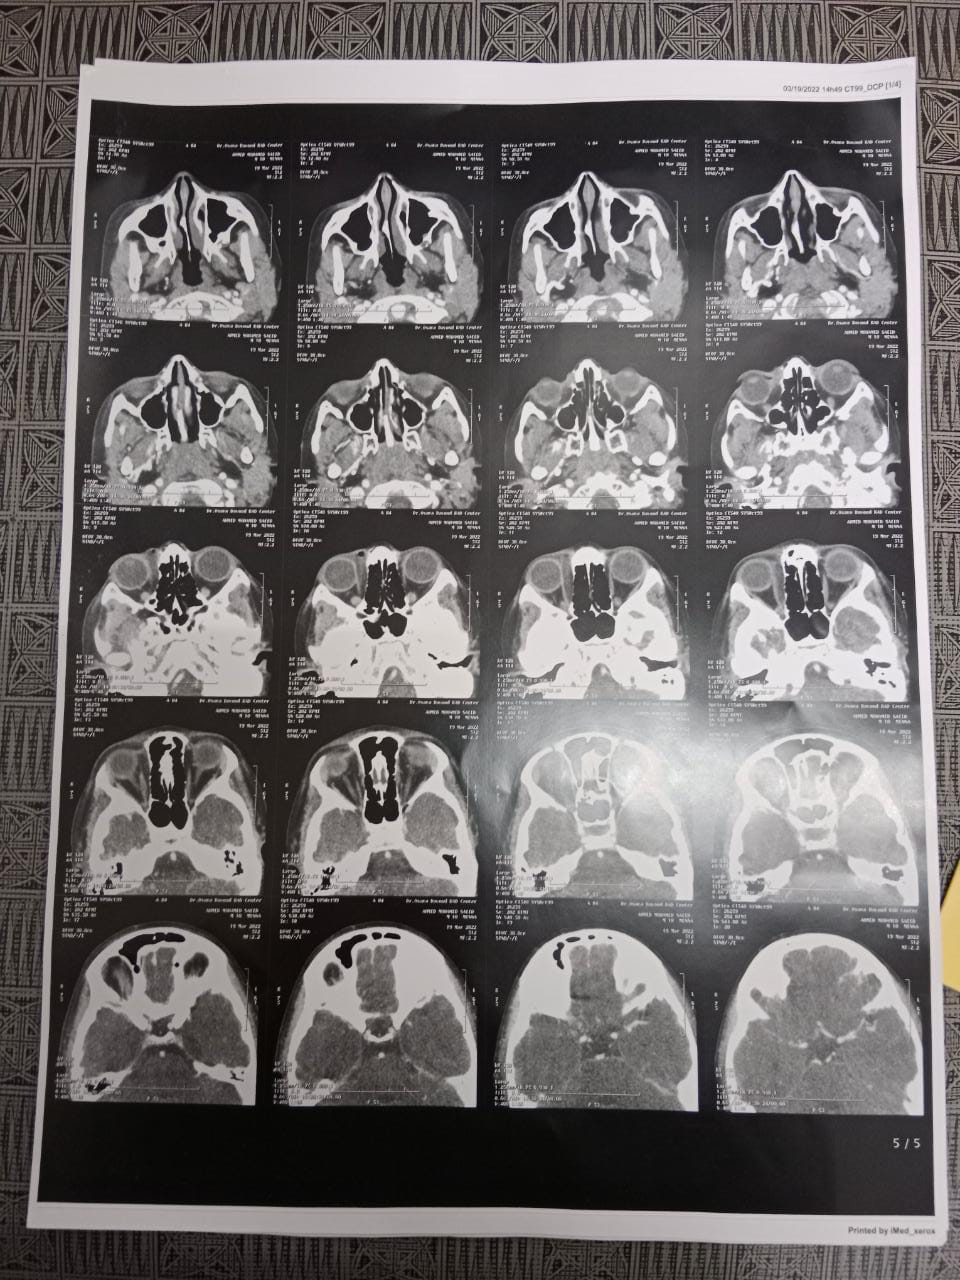

وأوضح الدكتور هشام شوقي مسعود، وكيل وزارة الصحة بمحافظة الشرقية، أن الفريق الطبي في مستشفى طب وجراحة العيون (الرمد) بمدينة الزقازيق، بمشاركة الدكتور أيمن عبدالغفار، والدكتور محجوب هلال، والدكتورة هالة عبده، أطباء الرمد في المستشفى، وهيئة التمريض بقسم العمليات الجراحية، بإشراف الدكتور محمد حسين، مدير مستشفى طب وجراحة العيون (الرمد) بمدينة الزقازيق، قد تمكنوا من إجراء عملية جراحية لاستخراج جسم غريب مُهمل داخل تجويف العين، والذي كان عبارة عن نصف قلم جاف، لطفل يبلغ من العمر 12 عامًا.

وأكد وكيل وزارة الصحة بمحافظة الشرقية، في بيانه، أن أهل الطفل المصاب كانوا يتوقعون أن الأمر عبارة عن كدمة منذ أكثر من شهرين، ولم يظهر جليًا من خلال الأشعة المقطعية، إلا أن الفريق الطبي قد تمكن من إجراء العملية الجراحية بنجاح واستخراج القلم، وسط حالة من الذهول من والدي الطفل.